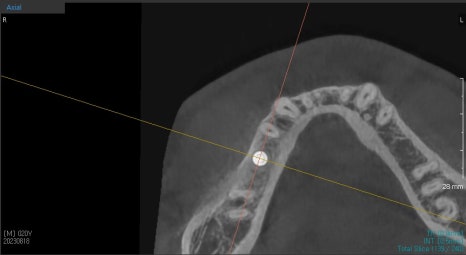

정확히 보기 위해 파노라마 엑스레이 사진을 찍었는데요.

빨간색 화살표 부분을 보시면

유치가 깨져서 일부가 남아있고,

후속 영구치가 없는 것을 확인 할 수가 있습니다.

유치의 뿌리도 다 녹아서 거의 남아있지 않으므로,

치료를 해서 쓸 수가 없는 상황인데요.